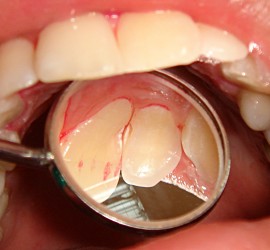

Ретроградный кариес. Кариозный процесс разрушает дентин со стороны пульпы. Наблюдается при наличии интактной, кариозной и пломбированной коронки, а также в случае гангрены пульпы кариозного и травматического происхождения. Со стороны полости пульпы идет процесс распада дентина за счет функции микроорганизмов и протеолитических ферментов. Ретроградный кариес может иметь место при хроническом пролиферативном […]